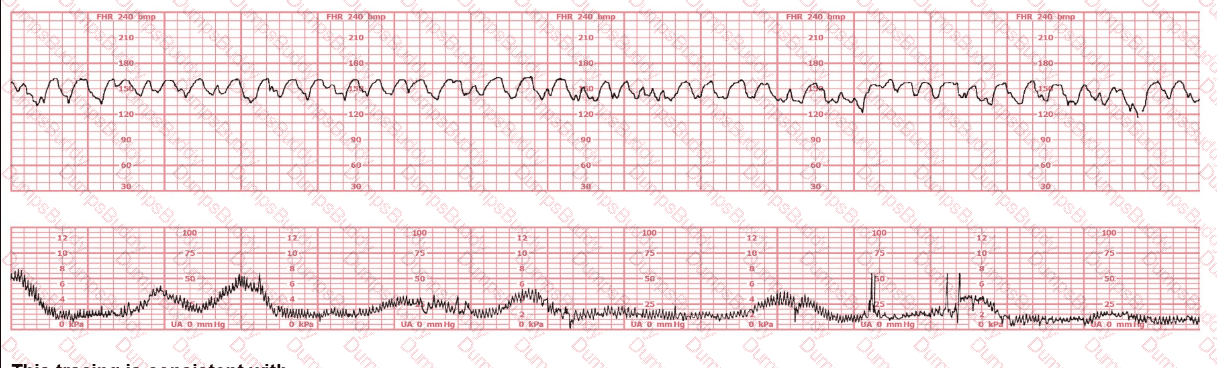

The decelerations seen in the fetal monitoring tracing shown are best described as: